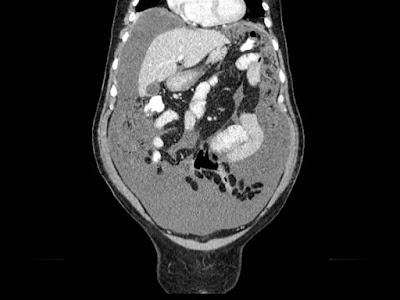

Paciente de 12 años con dolor abdominal. Remitida para estudio de masa intraabdominal.